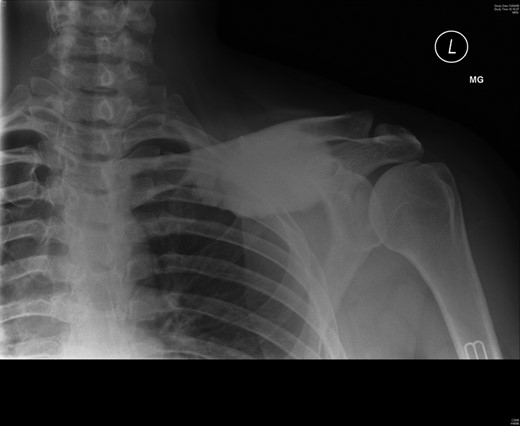

A 45-year-old woman presented with a 20-year history of a lump in the mid-third of the left clavicle, which had recently increased in size to 10 cm in diameter. Plain X-ray, computed tomography (CT) chest and clavicle, and bone scans were used to image the lesion (Figs 1–3). Radiology reported the lesion as a parosteal osteosarcoma, based on the CT appearance of tumour growing into the medulla of the mid-third of the clavicle; not usually a feature of an osteochondroma or an osteoma. Biopsies showed dense sclerotic bone, with no obvious malignant features. To confirm diagnosis complete excision of the tumour was needed, with a partial excision and scraping the lump off the surface deemed unsafe. The patient was informed that, following a total claviculectomy, a 30% functional loss (29.5% [8]) in her left shoulder power would be expected. Her active lifestyle meant this result was unacceptable, so she opted instead for excision of the tumour plus the adjacent clavicle, irradiation and reimplantation of the bone with internal fixation, despite this being relatively experimental. If successful, she would have virtually normal function. Although possible risks included infection or development of non-union, which would require further surgery or possible complete claviculectomy, it was deemed oncologically safe with a low risk of complications.

Preoperative CT scan, axial view showing the extent of the tumour.